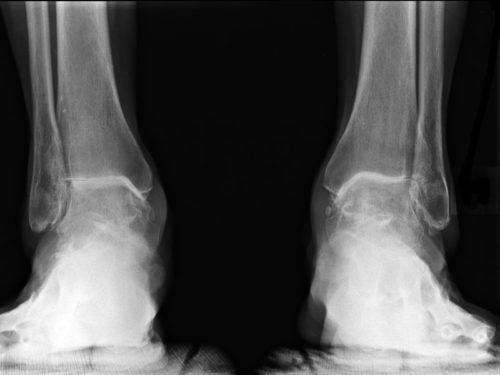

По мере прогрессирования артроз голеностопного сустава разделяют на три степени. 1 степень – болевые ощущения появляются после нагрузок, изредка наблюдается локальная отечность. На рентгенограмме видно легкое сужение просвета суставной щели.

Клиническая картина артроза 2 степени голеностопного сустава выражена постоянным болевым синдромом, который не зависит от физических нагрузок, ясно слышен хруст и поскрипывание в суставе при резких движениях. На рентгеновских снимках выражены деформации хряща, сужение суставной щели почти наполовину от естественной высоты.

Дальнейшее развитие артроза голеностопного сустава приводит к 3 степени патологии. Клиническая картина: интенсивные боли, продолжительность — до нескольких дней. Появляется хромота, голень отклоняется от анатомической оси вправо или влево. Рентгенограмма показывает атрофию связок и мышечной ткани, развитие остеофитов, деформацию в костной ткани.

Дальнейшее осложнение артроза приводит к деформации голеностопного сустава (внутрь или наружу). Двигательная активность нижней конечности сильно ограничена или отсутствует. Дистрофические процессы в голени способствуют образованию многочисленных остеофитов, которые сдавливают сосуды кровеносной системы и нервные корешки. Запущенное состояние патологии может привести к развитию тромбоза, синовита и других недугов.

- Первая стадия. Наличие сомнительных признаков остеоартроза на рентгенограмме. Изменения в самой структуре кости отсутствуют, но могут быть тени от различных уплотнений или, наоборот, размягчений тканей.

- Вторая стадия. Минимальные изменения строения сустава на рентгеновском снимке. К ним относится сужение суставной щели и признаки размягчения костной ткани.

- Третья стадия. Изменения сустава и околосуставных тканей средней выраженности. На снимке четко просматриваются изменения кости и хряща, характерные для артроза.

- Четвертая стадия. Выраженные изменения сустава и околосуставных тканей. К этой же стадии относят окостенение сустава и другие возможные осложнения и последствия артроза.

Простая радиография. С помощью рентгеновских лучей получают снимок голеностопа и оценивают состояние хряща. Таким способом проще всего определить дегенеративный процесс в суставе. Если у больного есть артрит, на снимке видно уменьшение суставной щели, структурные изменения хряща, пустоты в кости, остеофиты.